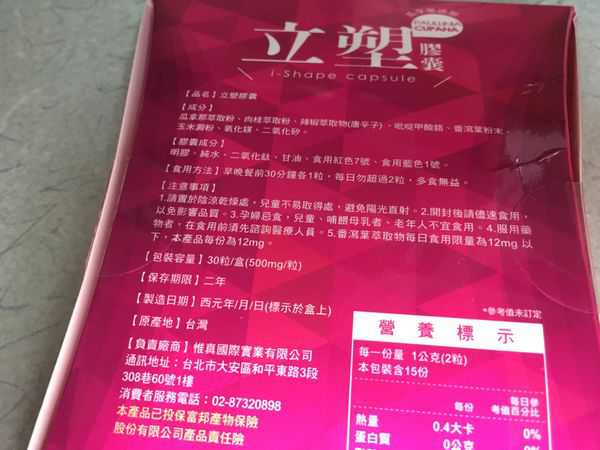

Supercut塑魔纖立塑膠囊的成分有:瓜拿那萃取粉、肉桂萃取粉、辣椒萃取物(唐辛子)、吡啶甲酸鉻、番瀉葉粉末、玉米澱粉、氧化鎂、二氧化矽。

之前上過相關課程,成分表是依照每項成分的多寡來排列順序,排在最前面的就是產品的主要成分!

食用方式:早晚餐前30分鐘各1粒,每日不超過2粒。(多食無益)

番瀉葉萃取物每日食用限量為12mg以下,

番瀉葉萃取物每日食用限量為12mg以下,